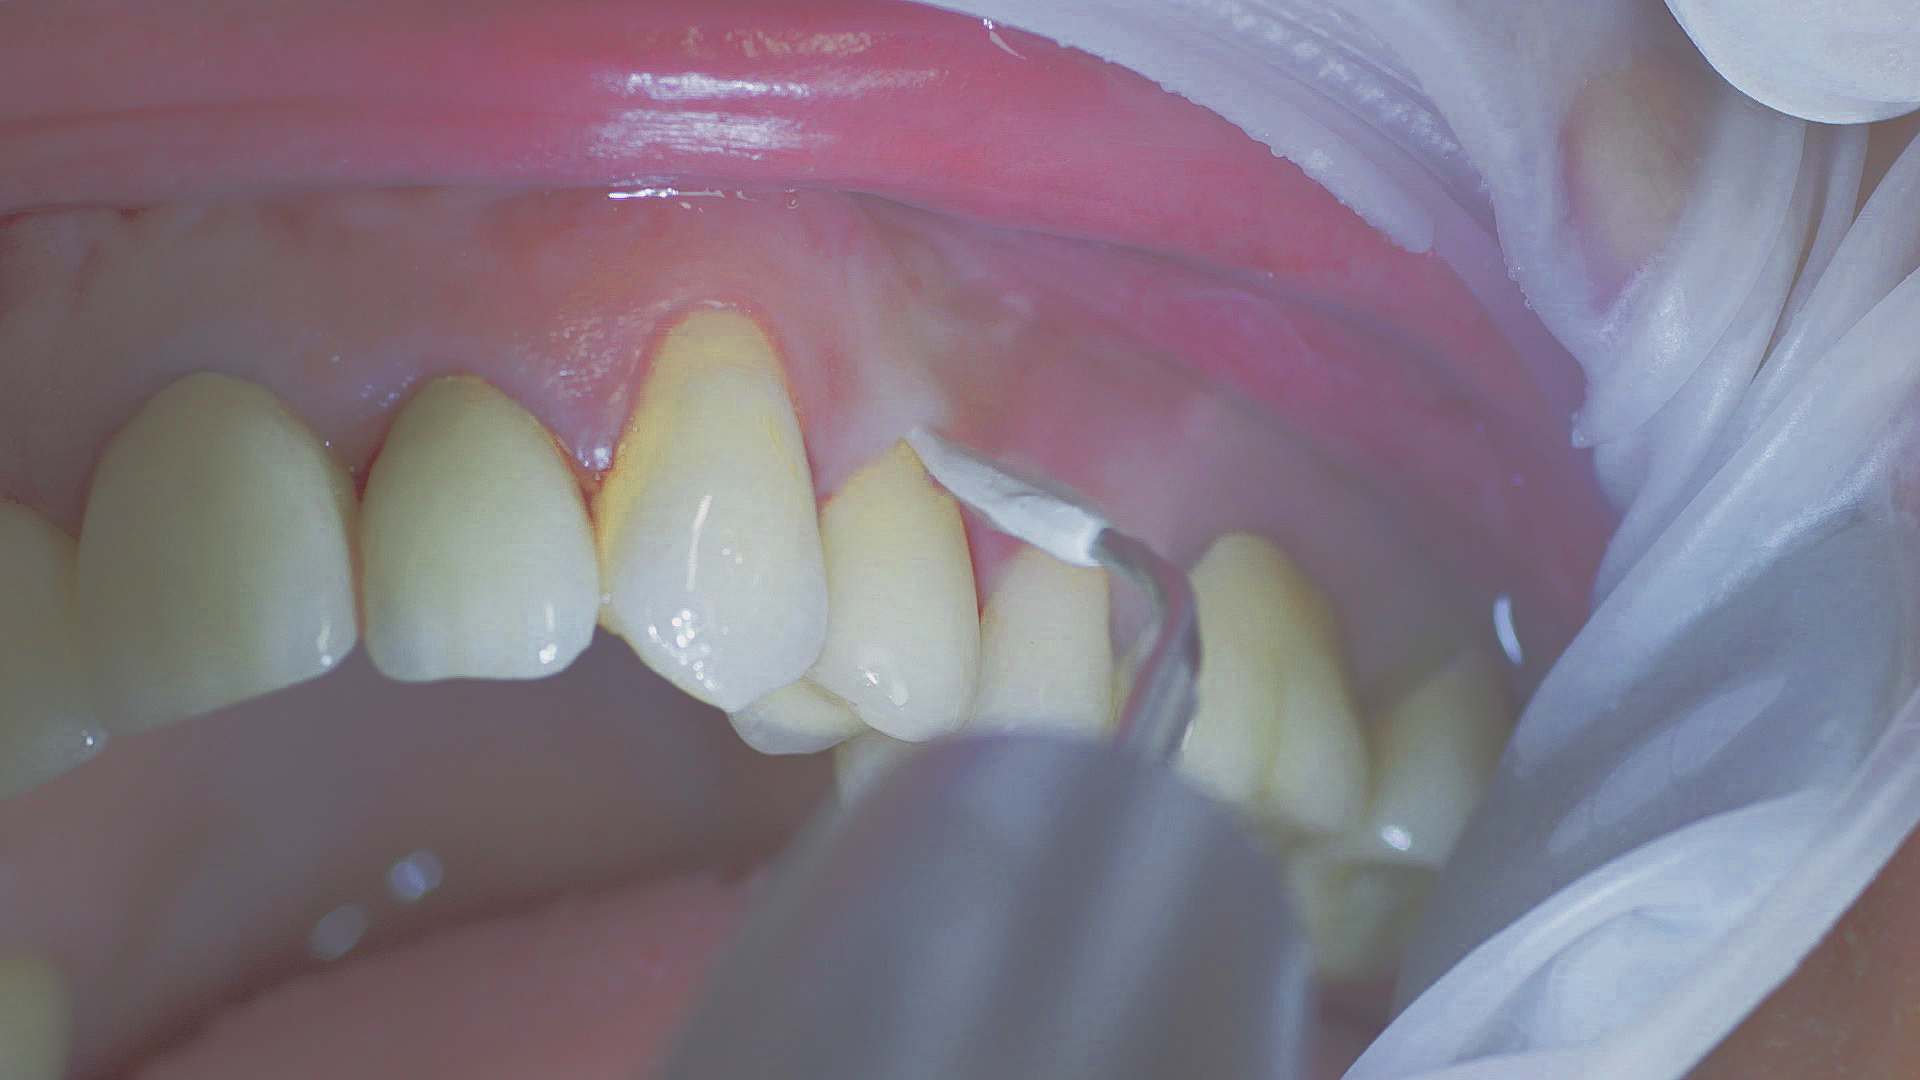

In the periodontal aftercare subsequent to implantation, soft (biofilm) and hard coatings are regularly professionally and mechanically removed.[16, 17] In the subgingival and supragingival areas, ultrasonic devices are generally used for this (Fig. 4), in combination with manual instruments where necessary. Alternatively, subgingival air polishing can be used in combination with periodontal attachments and powders.[18]

At-home oral hygiene should be carefully tailored to the new prosthesis and the patient accordingly instructed on this.[34] In combination with professional biofilm management, good preventative efficacy can be achieved in this way.[35] The risk of peri-implantitis decreases from 43.9 per cent (no recall) to 18.0 per cent if a patient receives a recall appointment carried out carefully each year, in other words by more than half.[36] Ultrasonic systems with special instruments that do not affect the materials are suitable for this, such as those made of PEEK (Fig. 5), or appropriate manual instruments.[37]